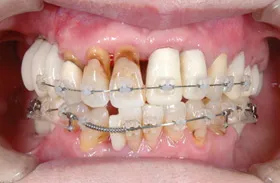

矯正、インプラントのための骨再生、歯の保存のための再生治療を組み合わせて治療を行った例

虫歯と重度の歯周炎(歯槽膿漏)、歯並びに悩まれていたケースです。

■初診時の全体写真

治療のポイント

歯並びを整え、咬合を回復するため、矯正治療を併せてを行いました。

歯が既に抜けていて、骨が吸収してしまっていた部分は、インプラントの埋入に十分な骨量を確保するための骨再生治療(GBR)を行いました。

歯周病によって、歯を支える歯周組織が破壊されてしまっていました。歯を保存するため、再生治療を行いました。

■治療前

■治療後

| 主訴 | 数年間、下の奥歯が無いため奥歯で咬めない 歯ならびが悪いため見た目が悪く口を開けて笑えないのとおいしく食事ができない 他院にて歯周病が治らないと言われた |

| 治療方法 | むし歯治療+骨再生療法(GBR)+矯正治療+インプラント治療+補綴治療 |

| 治療期間 | 約3年 |

| 通院回数等 | 約40回 |

| 費用 | 約500万円 |

| リスク・副作用 | 術後の腫れ・痛み |